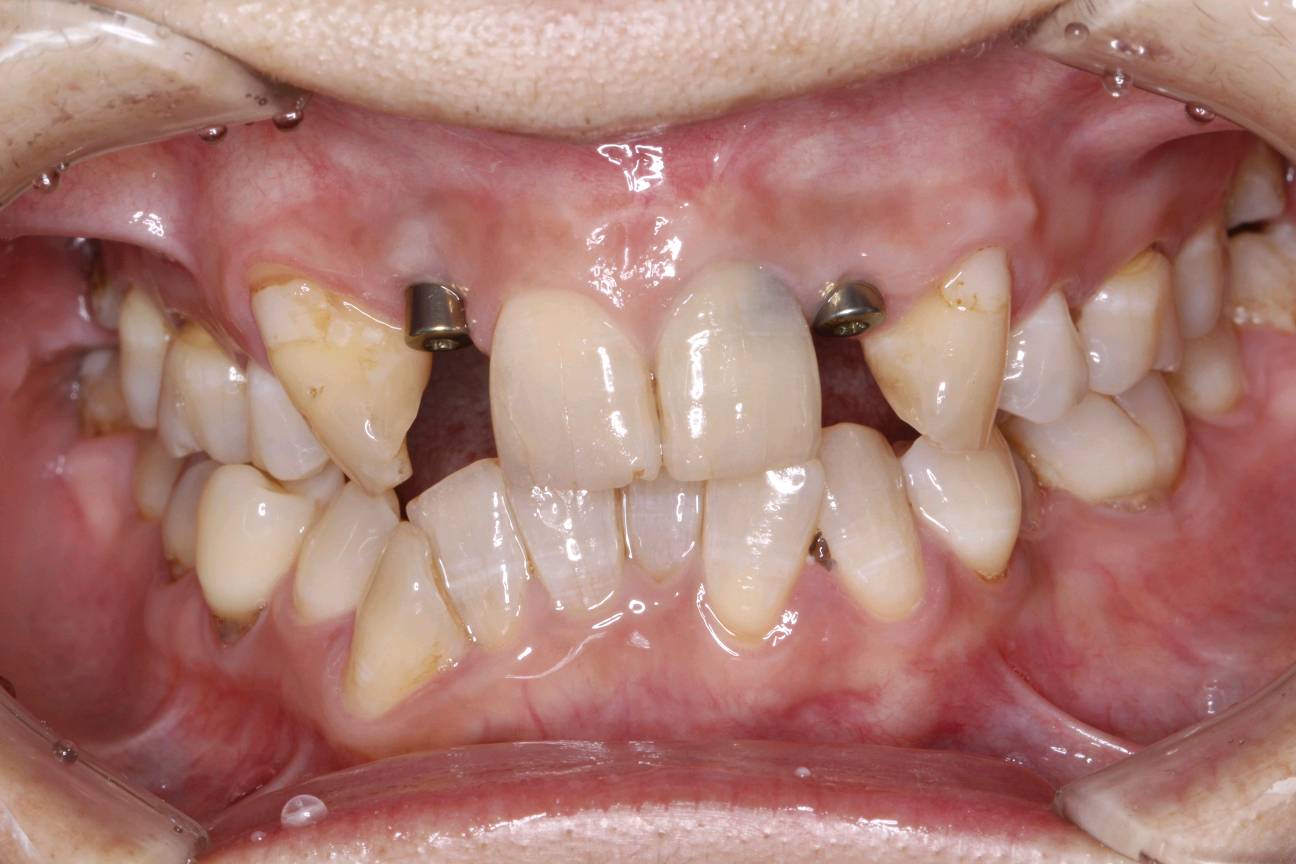

患者要求进行修复,恢复其美观行。而种植牙刚好可以满足患者需求。种植牙还可以获得与天然牙功能、结构以及美观十分相似的修复效果。今日如期佩戴牙齿,患者十分满意,重拾自信微笑。

自信笑容。

术后